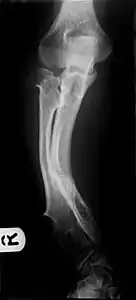

- Multiple osteochondromas causing deformity of the forearm (shortening of the Radius with secondary bowing of the Ulna).